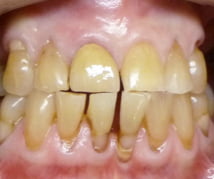

This was a difficult case of severe tooth wear. This was first stabilised and then following a course of whitening the teeth restored with cosmetic bonding. The young lady was delighted with her new smile.

Before

After